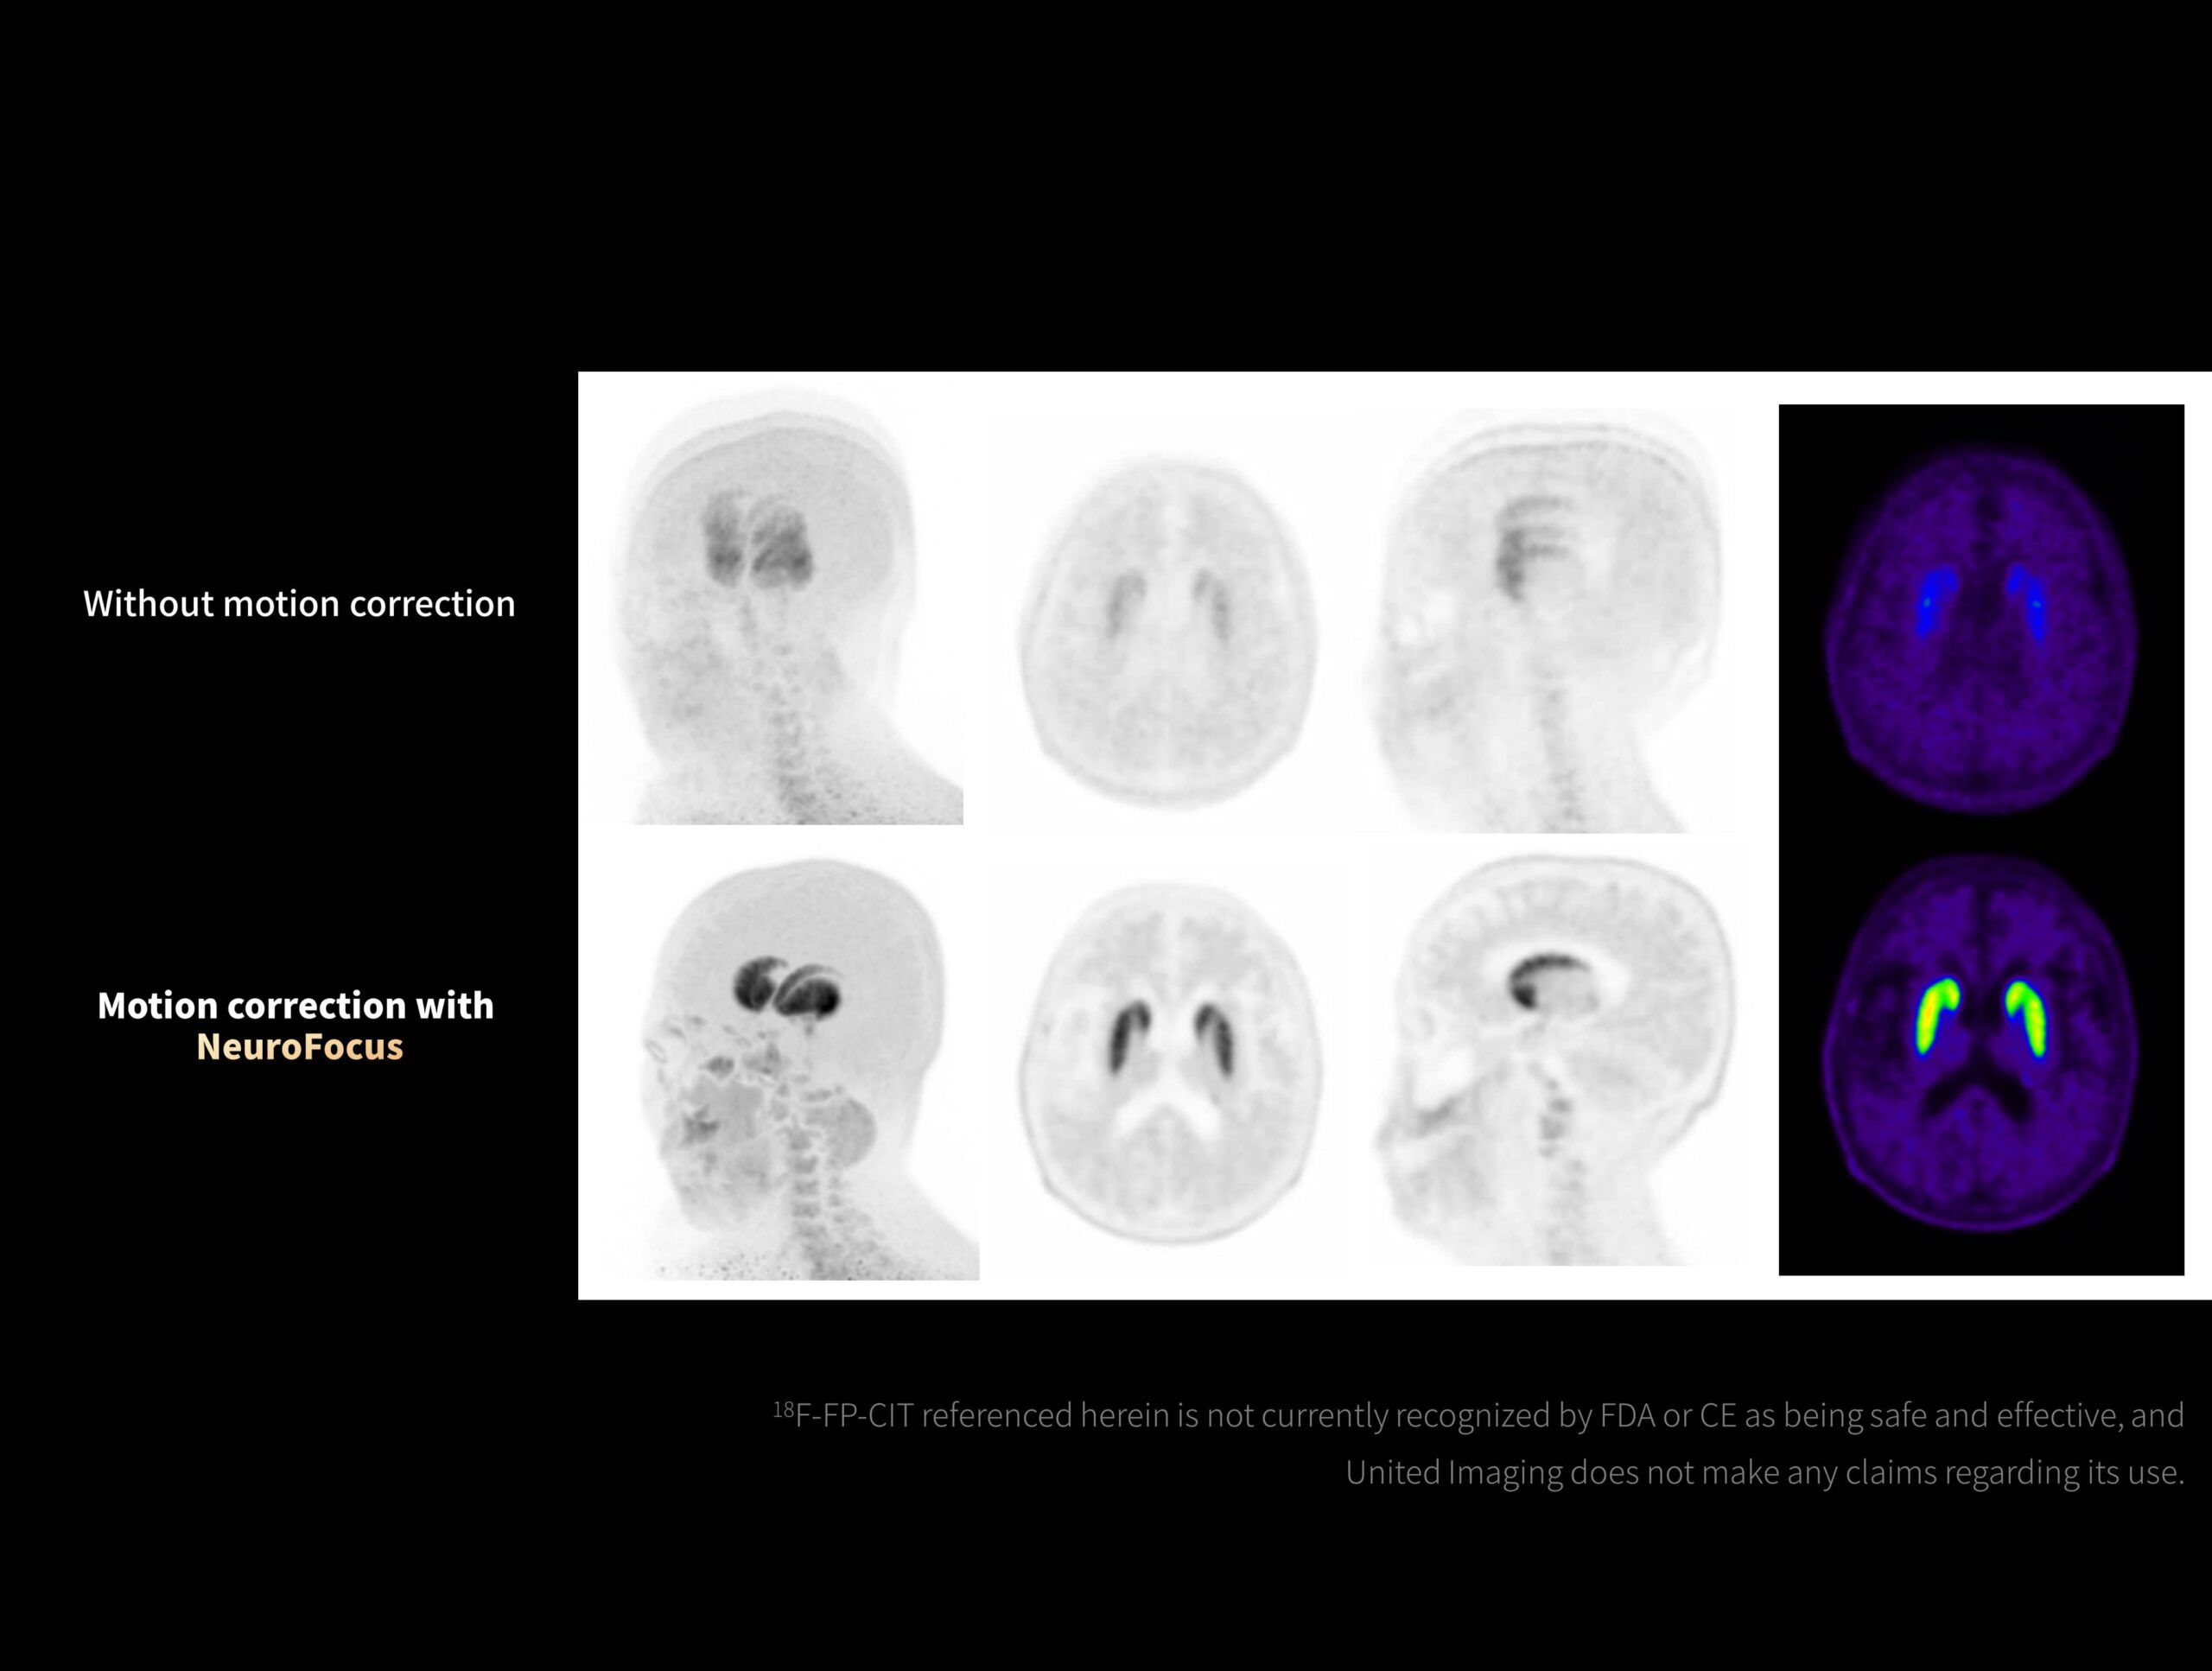

NeuroFocus corectează artefactele de mișcare în imagistica 18-F-FP-CIT